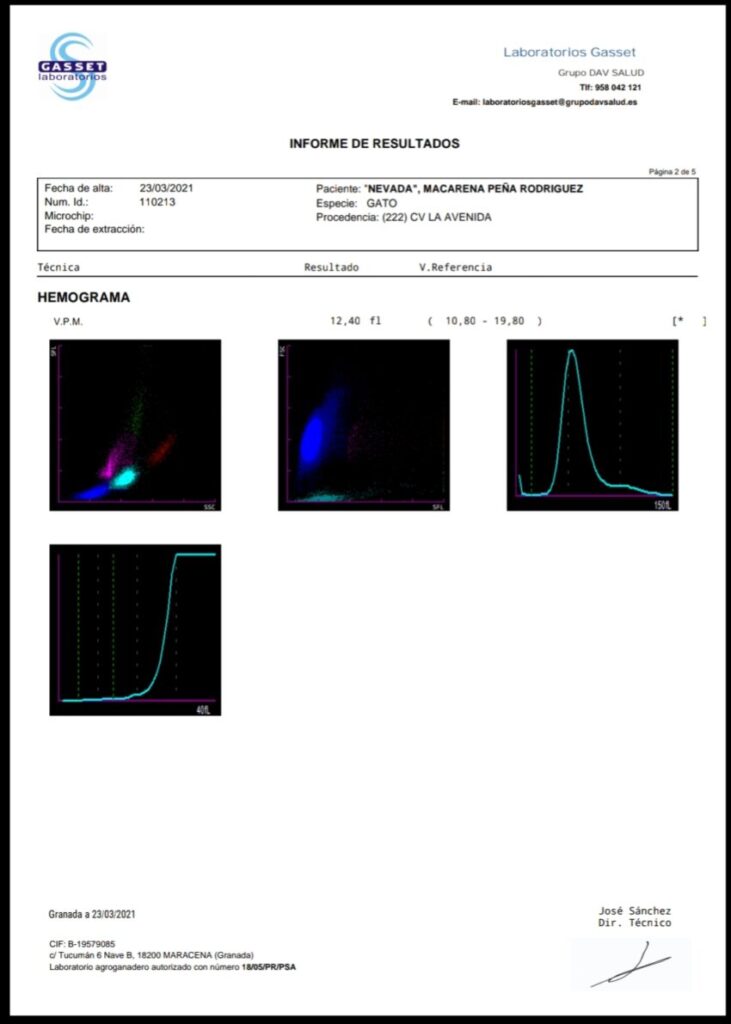

Ya tenenos los resultados de la sangre que se le extrajo. Es negativa a leucemina e inmuno, pero ha dado positivo en calcivirus y herpesvirus. Las heridas le van cicatrizando muy bien. Ella está enfadada. No le ha gustado un pelo que la hayamos secuestrado y la tengamos retenida. Ojalá tuviésemos manera de explicarle que lo hacemos por su bien